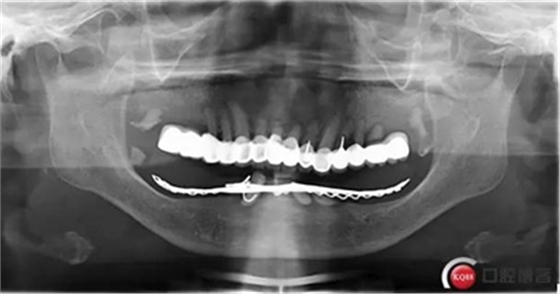

全過程約70日。因下牙槽骨較低,事前拍全景片。至今完成修復(fù)3個月,咀嚼效果良好。